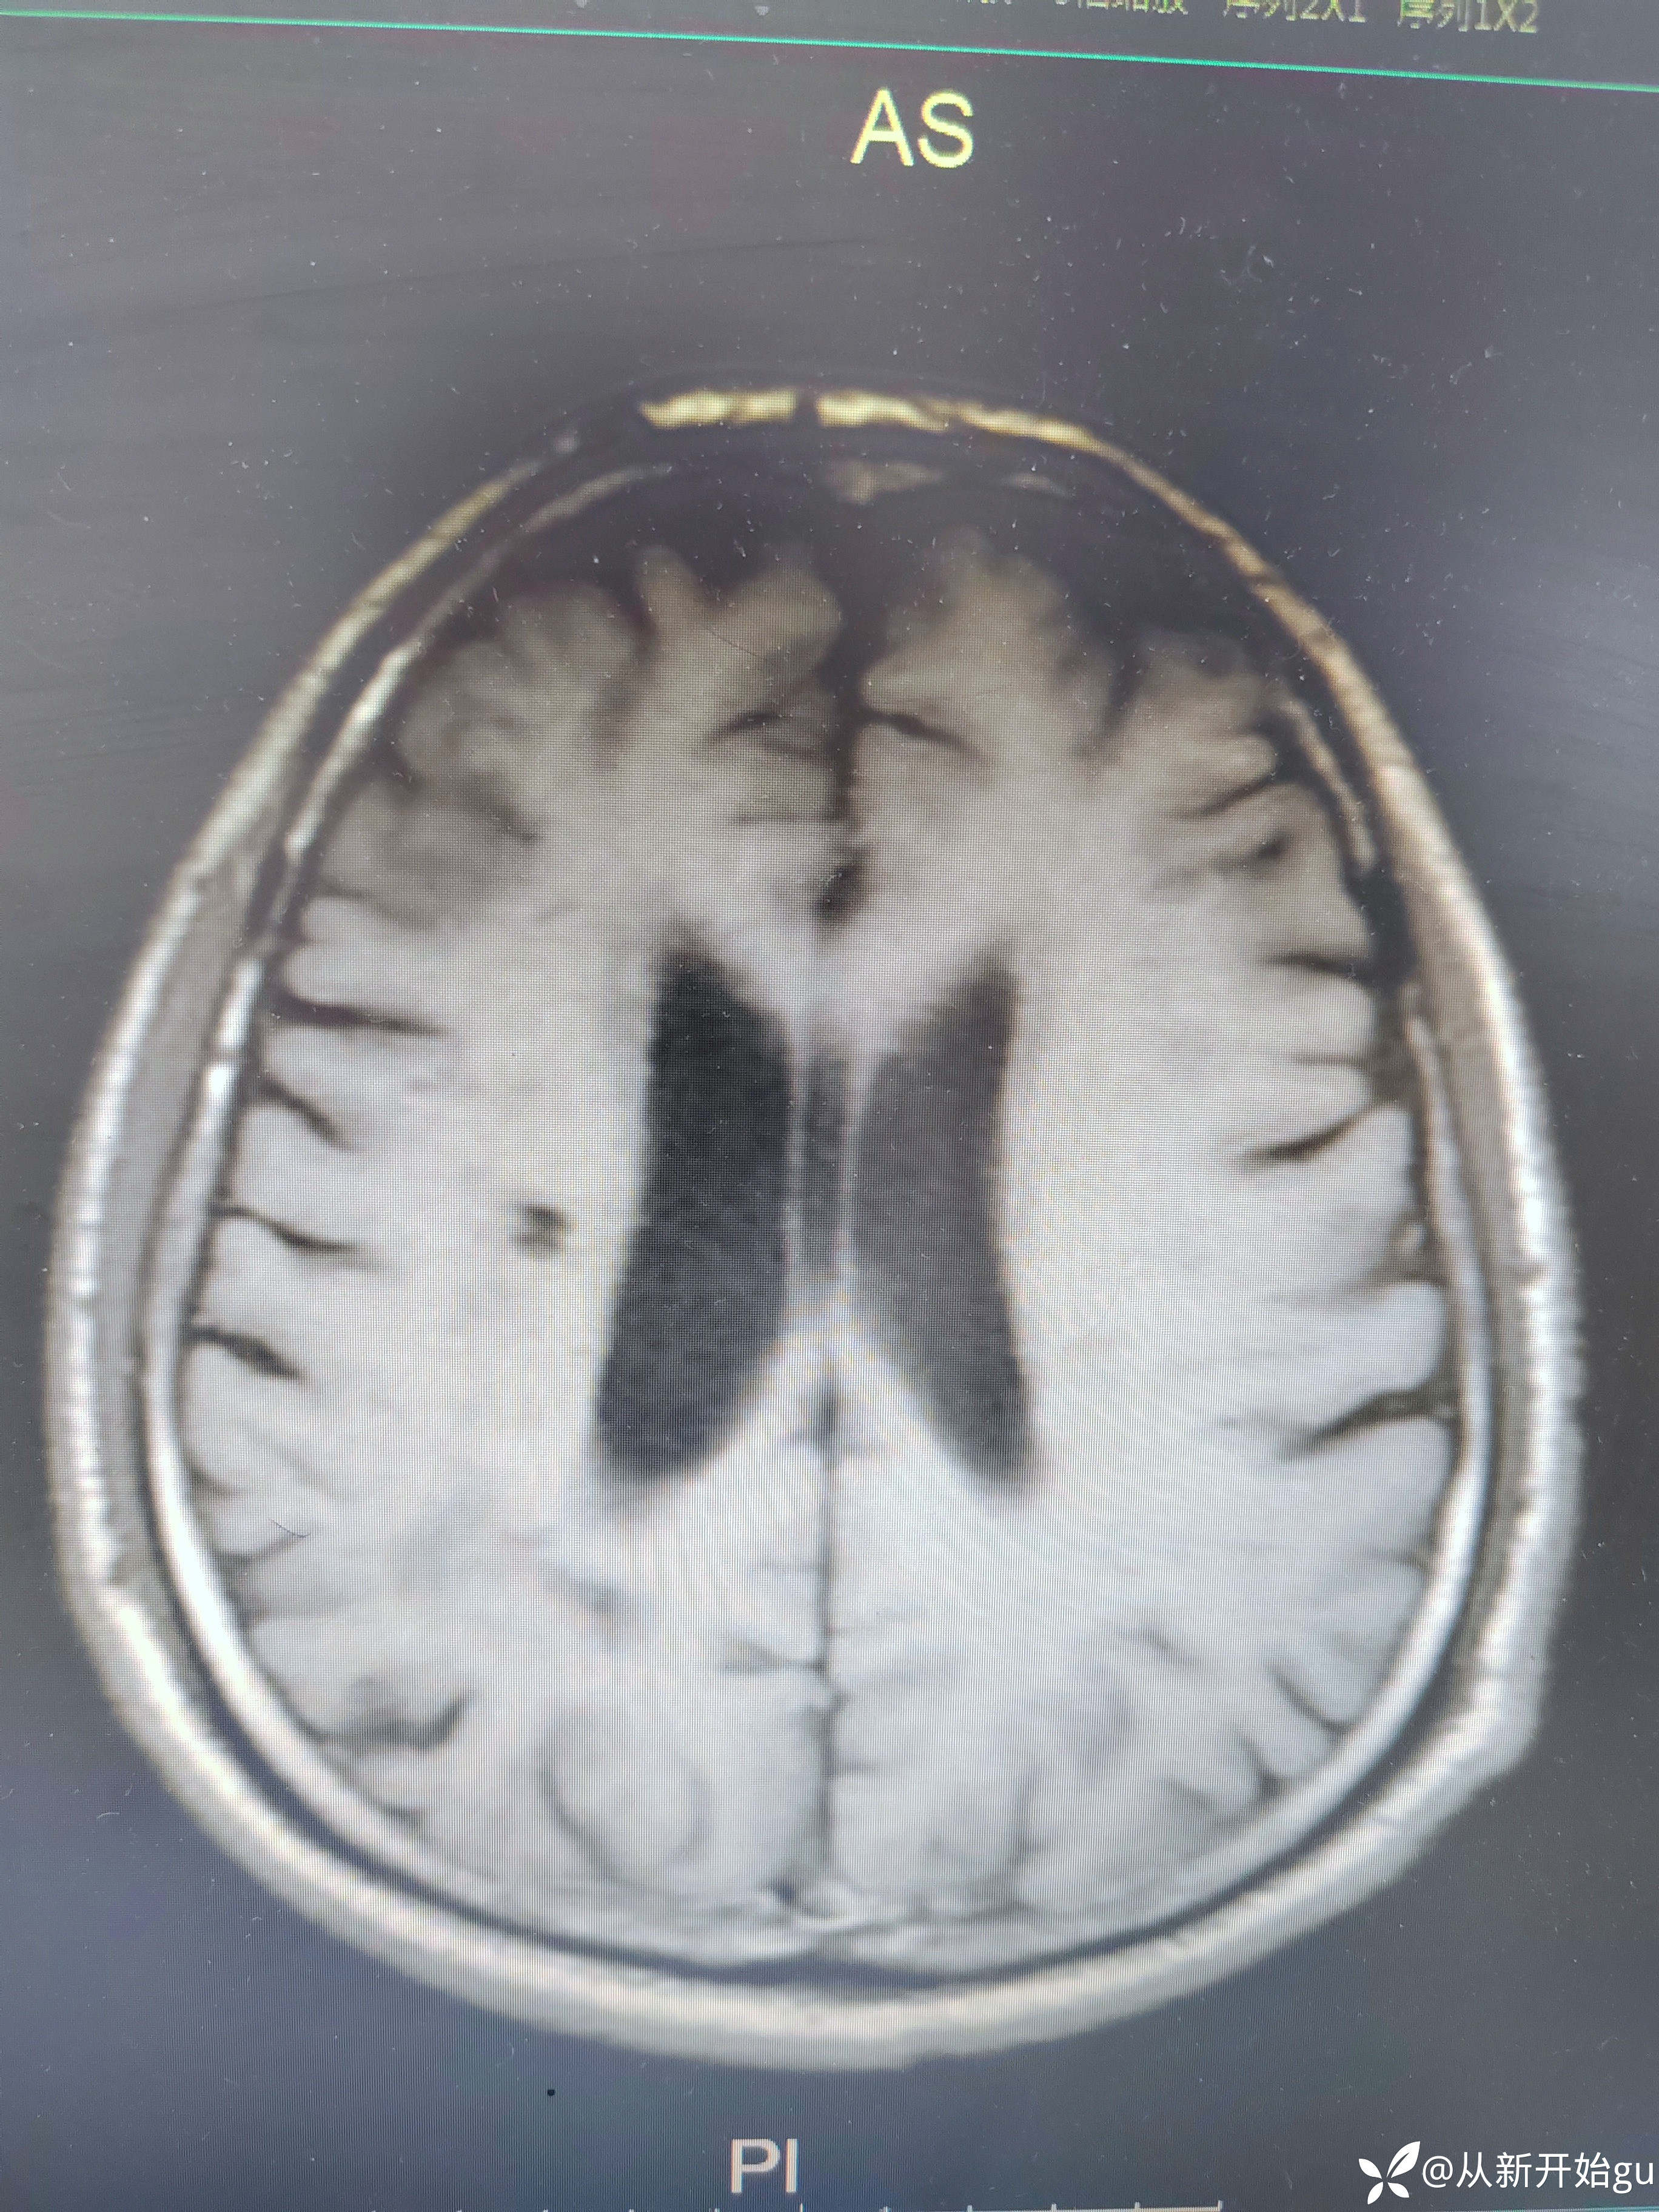

患者男性53岁,主因被发现左下肢活动障碍2.5小时来院,(患者下夜班,于上午9点休息,下午3点醒后出现症状)。既往脑梗死病史9个月,遗留言语不利及口角歪斜的症状。查体:右侧鼻唇沟稍浅,神舌右偏,左侧下肢肌力4级,左侧指鼻试验欠稳准,左侧巴氏征阳性。外院完善颅脑CT无出血改变。来院后完善核磁检查如图所示。